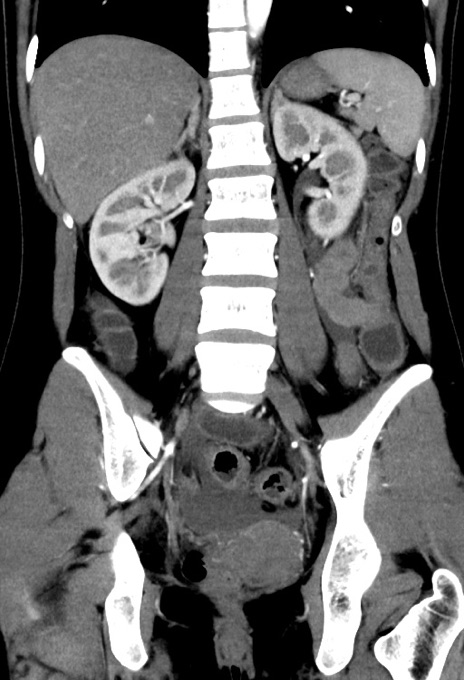

症例17(冠状断像)

【症例】20歳代女性

【主訴】嘔吐、下腹部痛

【現病歴】昨日夕食後に嘔吐し下腹部痛が出現。本日になっても嘔吐持続し改善しないため来院。

【身体所見】意識清明、BT 37.2℃、BP 108/67mmHg、腹部:平坦、やや硬、下腹部正中から右にかけて圧痛あり、反跳痛軽度あり、tapping pain(+)。

【データ】WBC 13600、CRP 14.94